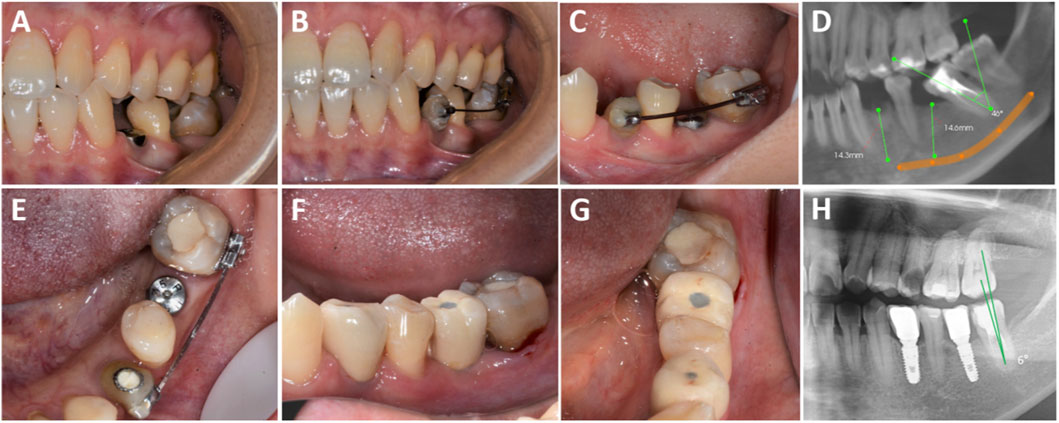

Abstract Background Tooth loss accompanied by adjacent tooth inclination or rotation presents a biomechanical challenge in combined orthodontic–implant rehabilitation. Whether "implant-first anchorage" provides superior clinical efficiency and biological benefits compared with the conventional "orthodontics-first then implant" pathway remains uncertain. Methods A retrospective cohort study was conducted based on cases treated between January 2019 and December 2024 by the Departments of Implantology and Orthodontics at the Affiliated Stomatological Hospital of Jinan University. Patients with partial edentulism and localized malalignment were allocated into two cohorts according to the actual treatment pathway received: implant-first (n=20) versus orthodontics-first (n=20). Clinical data were extracted from medical records and radiographs. Primary outcomes included treatment duration, cost, and patient-reported satisfaction (VAS). Secondary outcomes comprised periodontal parameters (mPLI, SBI, PD), adjacent tooth inclination, alveolar crest height, and number of visits. Results Compared with the orthodontics-first cohort, the implant-first cohort showed a markedly shorter time for local alignment (5.00±1.25 vs 11.78±2.35 months, P<0.001), lower overall cost (3000.00±0.00 vs 6100.00±680.56 RMB, P<0.001), fewer visits (8.20±1.32 vs 15.10±2.49, P<0.001), and higher satisfaction (8.05±1.32 vs 6.10±1.68, P<0.001). Periodontal metrics were consistently more favorable in the implant-first cohort (mPLI 1.20±0.36 vs 3.05±0.50; SBI 0.96±0.46 vs 1.89±0.39; PD 2.09±0.37 vs 2.67±0.33; all P<0.01). Changes in adjacent tooth inclination and space